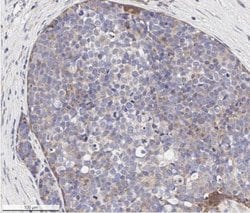

| Immunohistochemistry (Paraffin), Western Blot, Immunocytochemistry | |